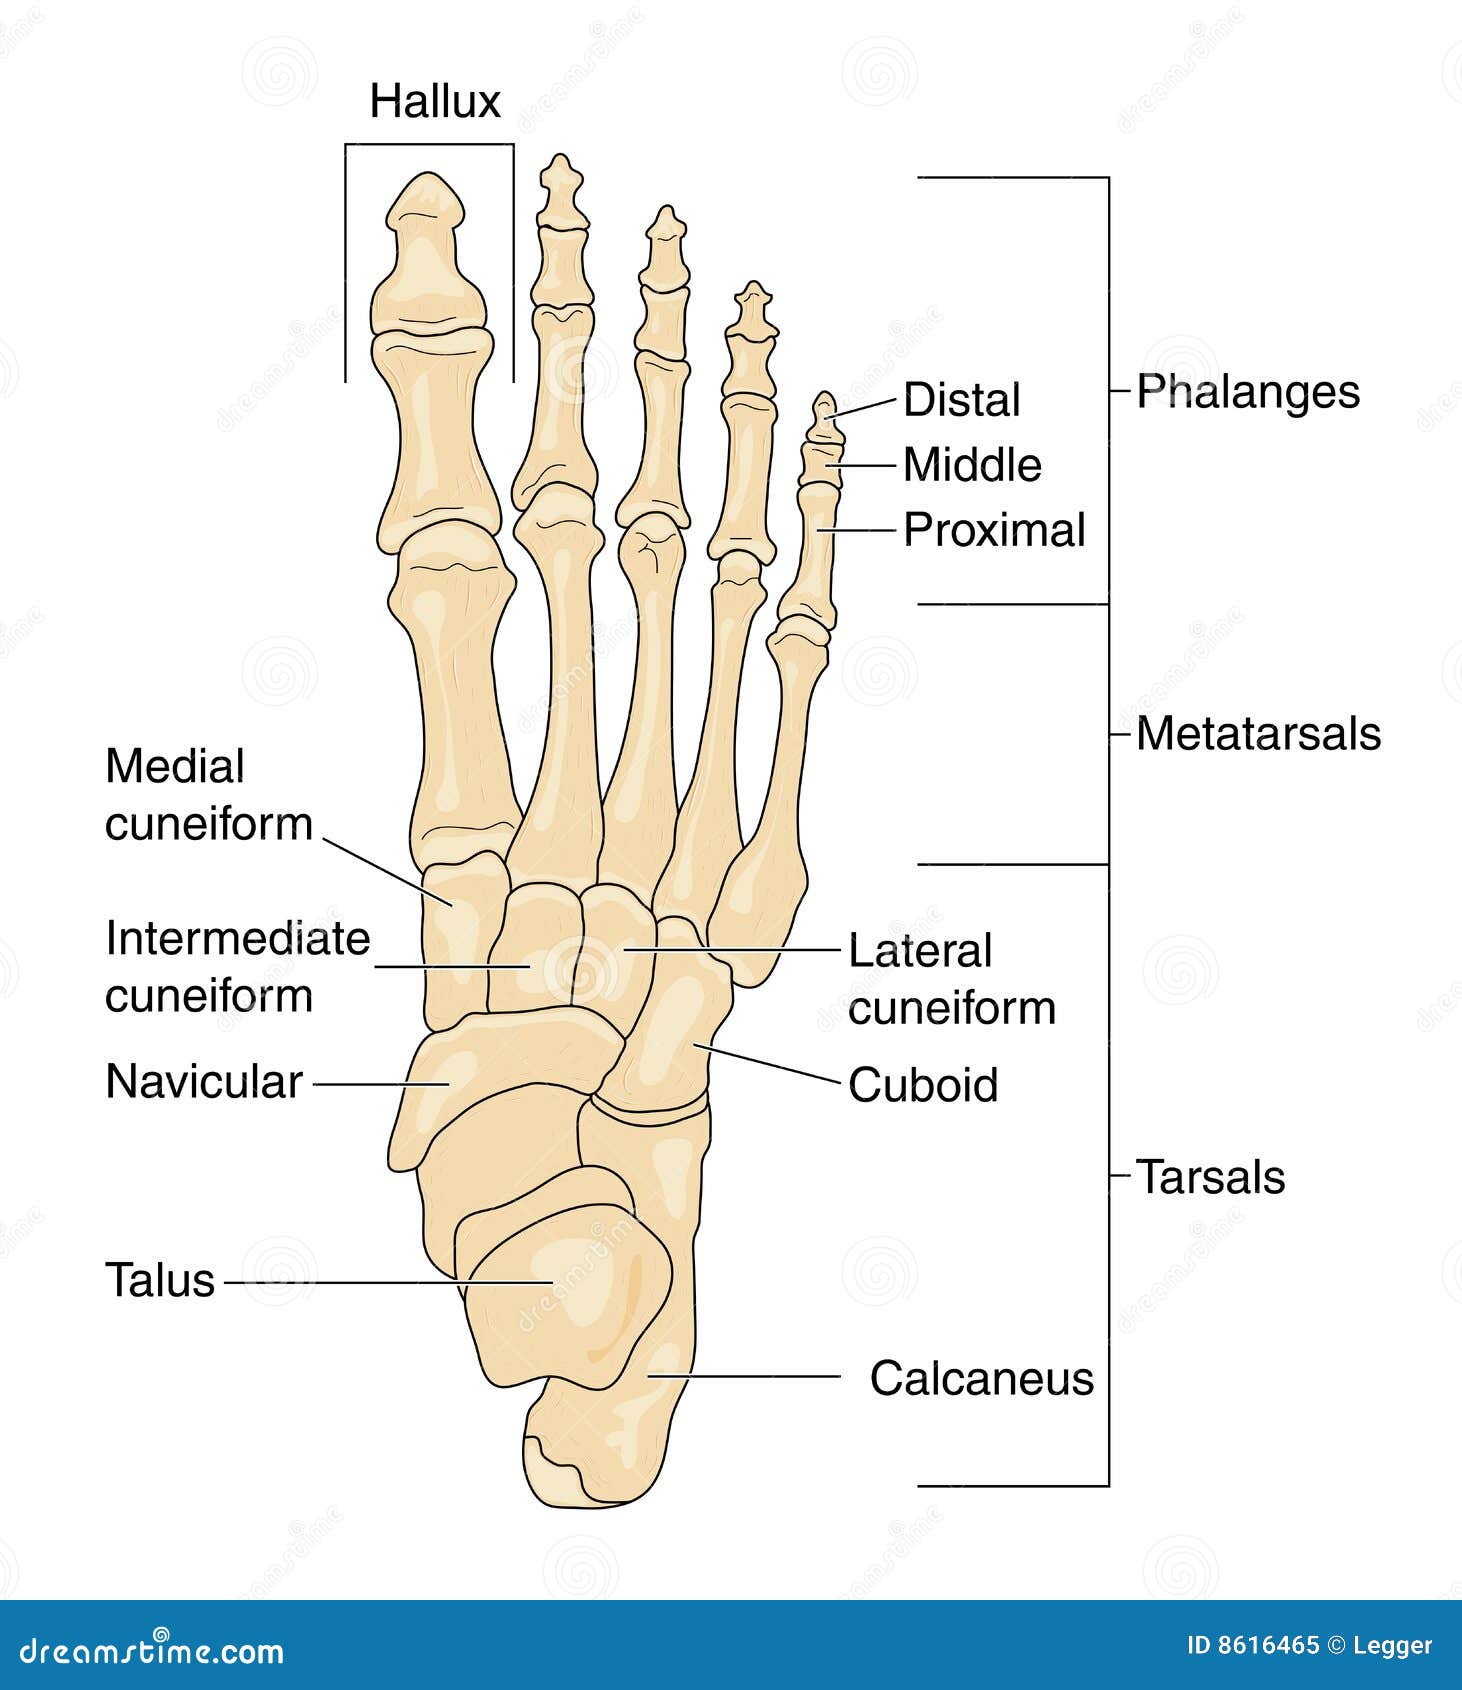

Anatomia Delle Ossa Dei Piedi Illustrazione Di Stock - Illustrazione Di

it.dreamstime.comFoot Bones With Explanation. Stock Vector - Image: 65669090

it.dreamstime.comFoot Bones With Explanation. Stock Vector - Image: 65669090

dreamstime.compiede ossa anatomie verklaring spiegazione explication explanation segno

dreamstime.compiede ossa anatomie verklaring spiegazione explication explanation segno

Anatomia Delle Ossa Dei Piedi Illustrazione Vettoriale - Illustrazione

Bones Of The Foot, Labeled Royalty Free Stock Photo - Image: 8616465

www.dreamstime.compiede ossa knochen foot beschriftet fusses contrassegnate calcaneus phalanges fersenbein tarsals fußes anatomy

www.dreamstime.compiede ossa knochen foot beschriftet fusses contrassegnate calcaneus phalanges fersenbein tarsals fußes anatomy